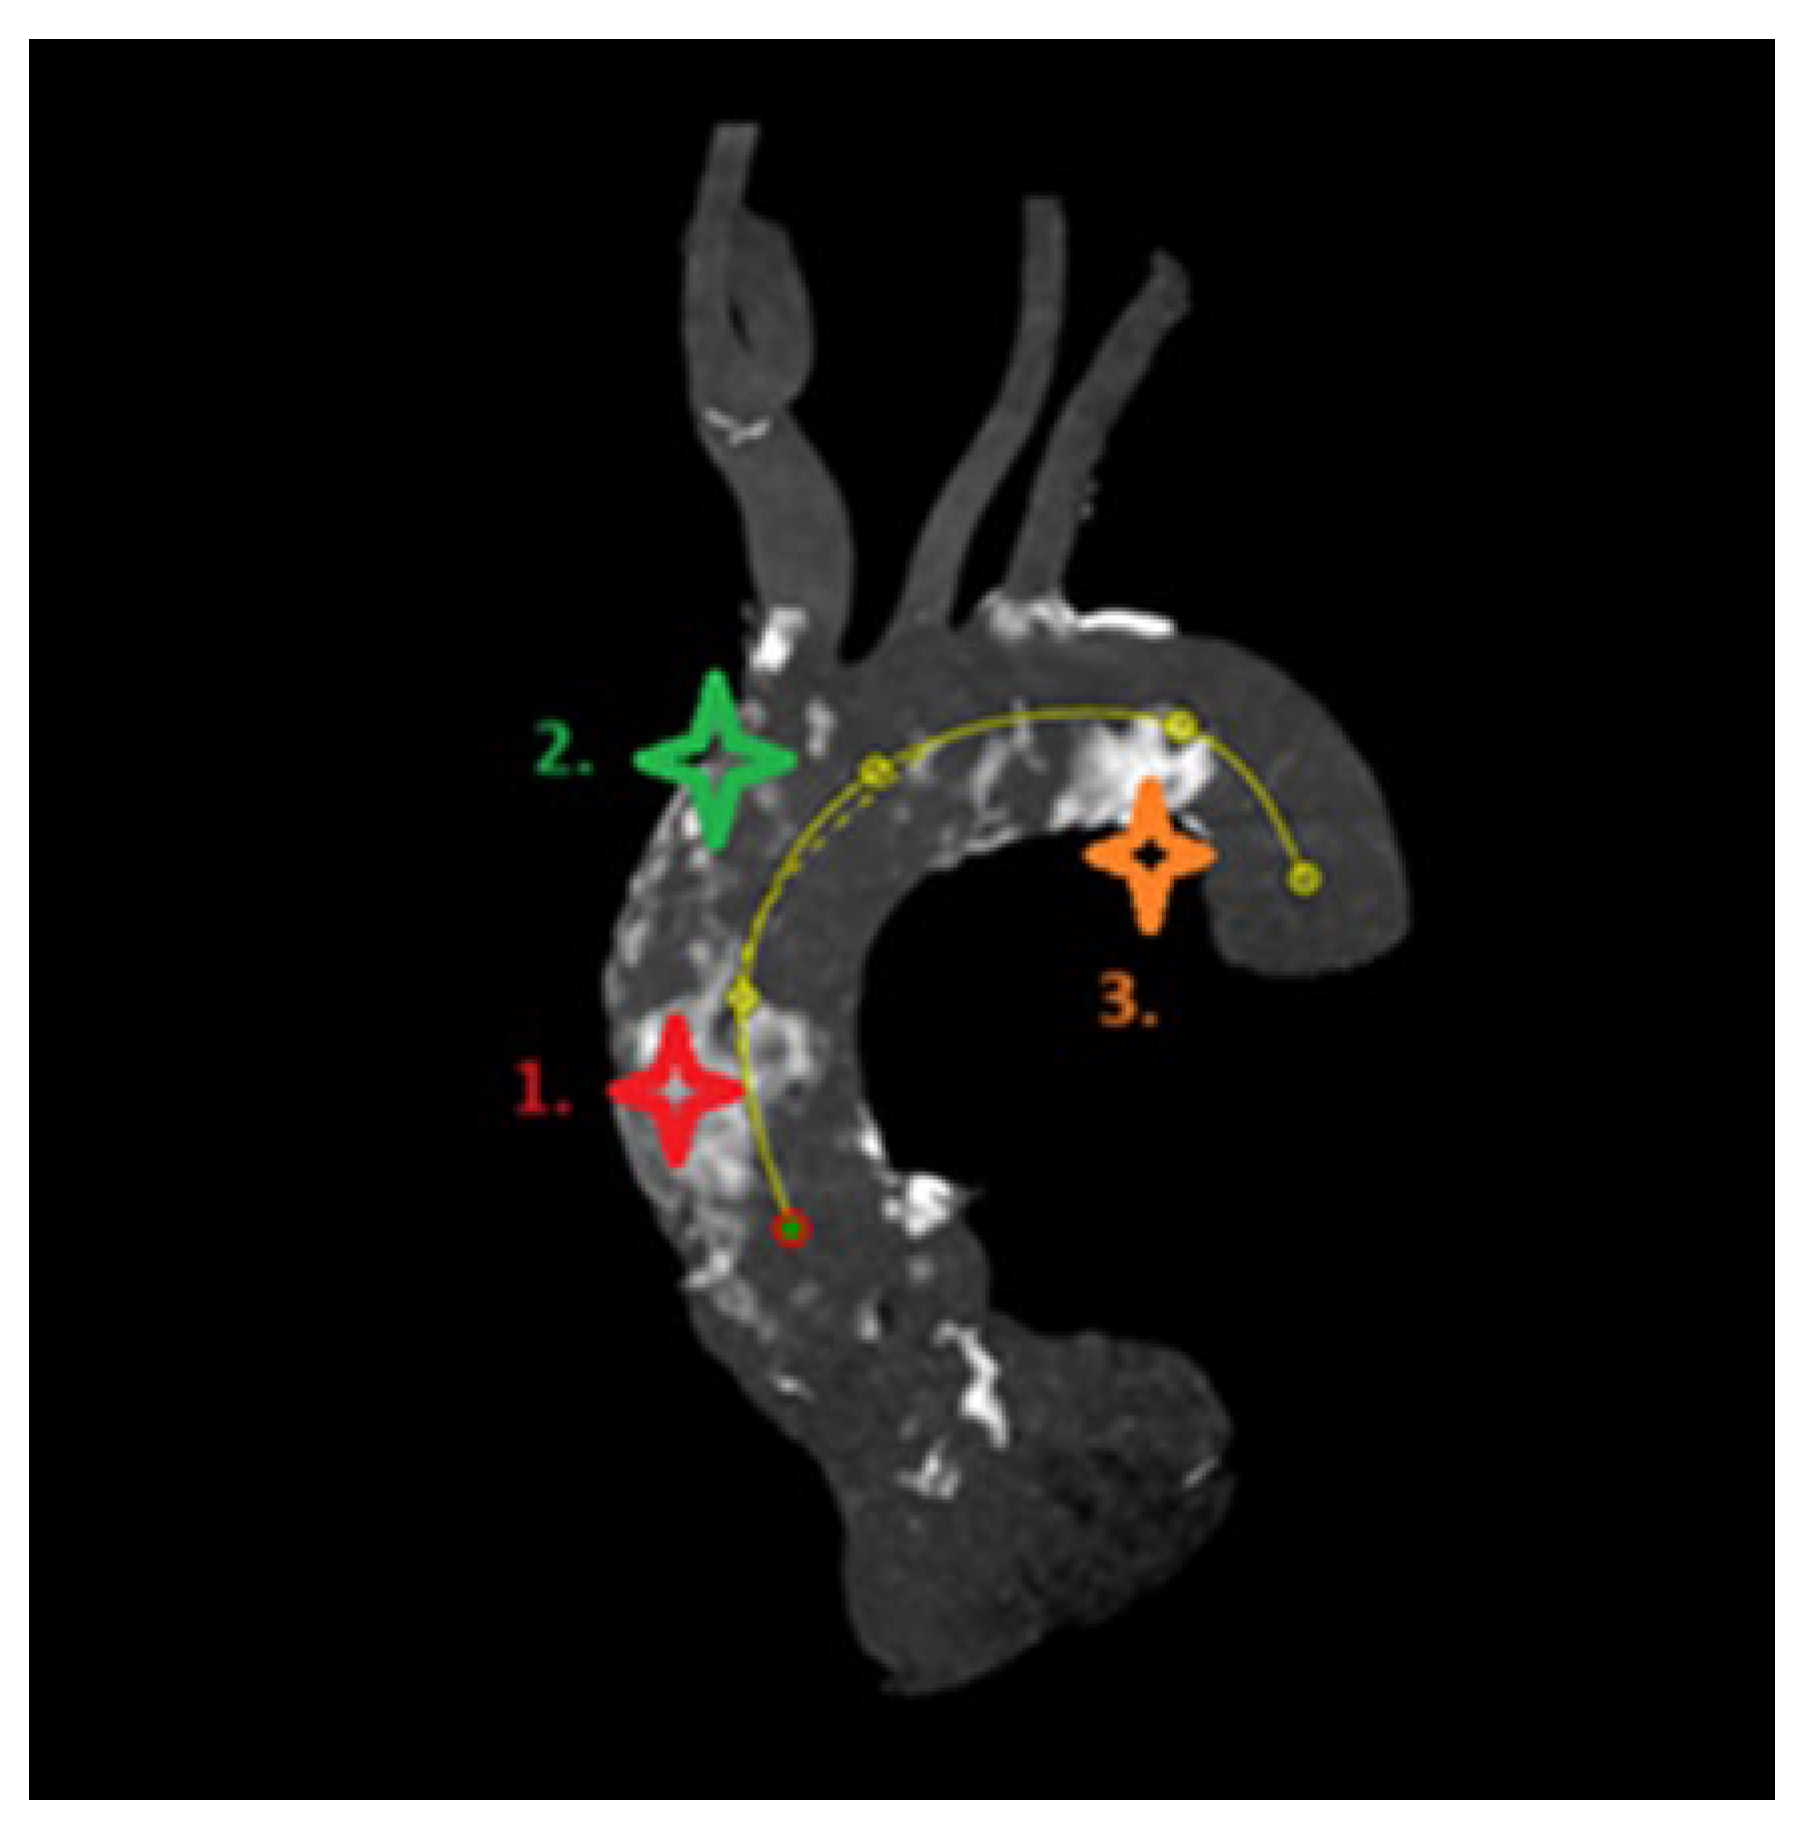

- (1)

- Proximal segment, from sinotubular junction to mid-ascending aorta (at level of pulmonary artery bifurcation);

- (2)

- Middle segment, from mid-ascending aorta (at pulmonary artery bifurcation) to origin of brachiocephalic trunk;

- (3)

- Distal segment, from origin of brachiocephalic trunk to origin of left subclavian artery.